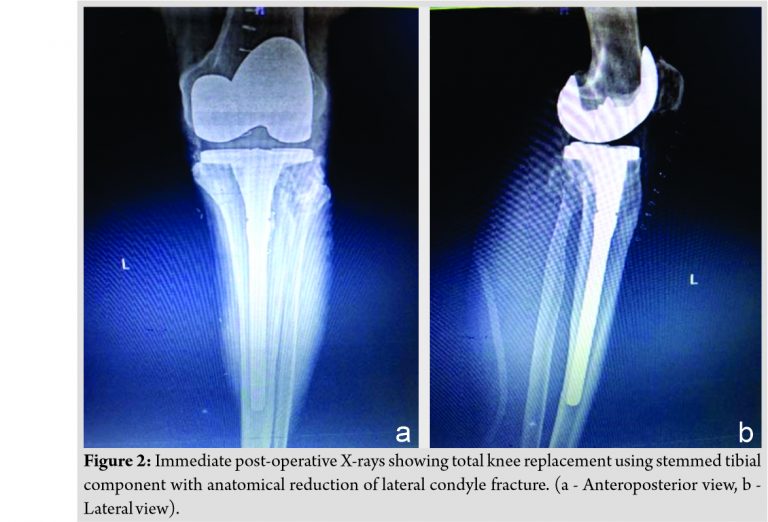

After getting the fitness for surgery (40 days after the trauma), the patient was operated in supine position through medial parapatellar approach using tourniquet. After the femur preparation, tibial preparation was started with removal of fibrous tissue at the fracture site, anatomical reduction of fracture, and maintaining the reduction with reduction forceps till the completion of the tibial preparation to prevent the displacement of fracture fragment. Cemented TKR was done using Zimmer implant of femoral component size E, tibial component of size 4 with stem extension of 12 mm diameter × 155 mm length and articular surface height of 10 mm (Fig. 2a and b). As the fracture was properly reduced to anatomical position and there was only fracture split, no depression, the augmentation was not required. Wound was closed in layers and the patient was given long knee brace postoperatively. Partial weight-bearing and knee range of motion were started after 3 days and full weight-bearing was started after 3 weeks. Eight months post-operative X-rays (Fig. 3a and b) showed healing of lateral condyle fracture and without any loosening of implants. The patient is having good knee range of movements and no pain on weight-bearing at present (Fig. 4a and b).